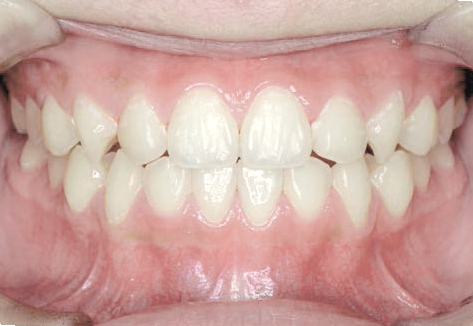

出っ歯

八重歯になっちゃった…歯が入る隙間がないけど、永久歯は抜きたくない!

Aさん (矯正開始時:9歳)

Before

After

すっきりしたお顔立ちの女の子ですが、外側から八重歯が生えてきてしまいました。

治療を終えて

マイオブレイスとBWS装置を使い、あごの骨や歯並びの形を整えながら、鼻呼吸や正しい飲み込み方も身に付けることができました。

お口の悪いクセは改善され、お子さん自身の力でしっかりとしたかみ合わせができるようになりました。ご希望通り永久歯を抜く必要はありませんでした。

主訴・治療内容 他院で「永久歯を抜いて矯正」をすすめられたが抜歯に抵抗があり「永久歯を抜かずに、あごの骨から整えてくれる」と口コミを見て当院を選んでくださいました。

治療期間 2年

費用 495,000円(税込)